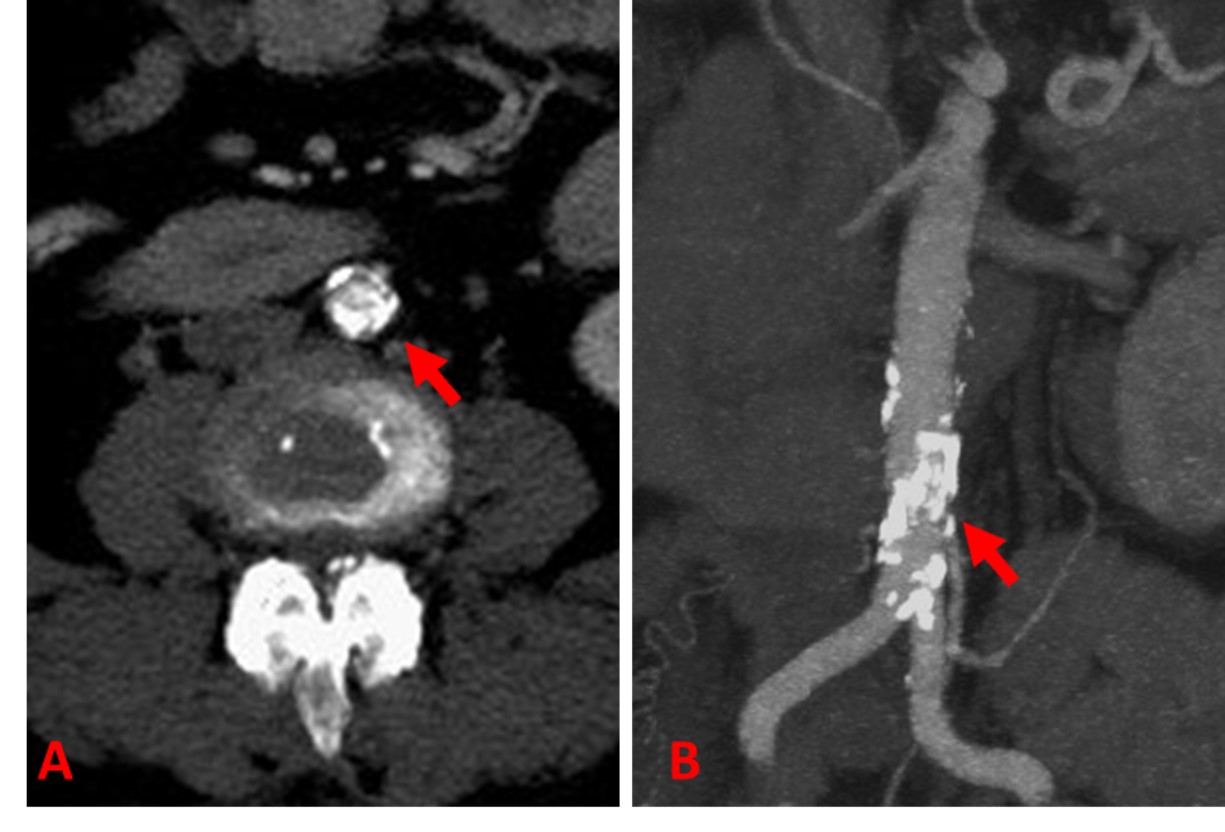

A 61-year-old female presented with a two-month history of right foot pain and discoloration of the first and fifth toe. On questioning, she also noted a history of significant short distance thigh and buttock claudication for the last several months. She was relatively healthy at baseline with a history of hypertension and hyperlipidemia, but a substantial smoking history of two and a half packs per day for 30 years. Her surgical history was notable only for a previous back surgery. On examination, she had reddish discoloration of her right first and fifth toes. She also had no palpable femoral or distal lower extremity pulses. Noninvasive vascular testing revealed flattened pulse volume recording bilaterally from the high thigh to the digit suggesting significant aortoiliac disease. A CTA of the abdomen and pelvis with runoff was obtained which showed a nearly occlusive coral reef-like plaque isolated to the distal aorta just above the bifurcation with some mural thrombus extending proximally close to the level of the renal arteries and essentially normal iliac arteries and distal runoff. (Figure 1) Preoperative testing included a normal stress test.

Figure 1: Preoperative CT arteriogram demonstrate a bulky, heavily and circumferentially calcified obstruction in the infrarenal abdominal aorta (A). On MIP reconstructions (B), the plaque is seen as focused within the infrarenal segment extending to the bifurcation, but sparing the iliac vessels.